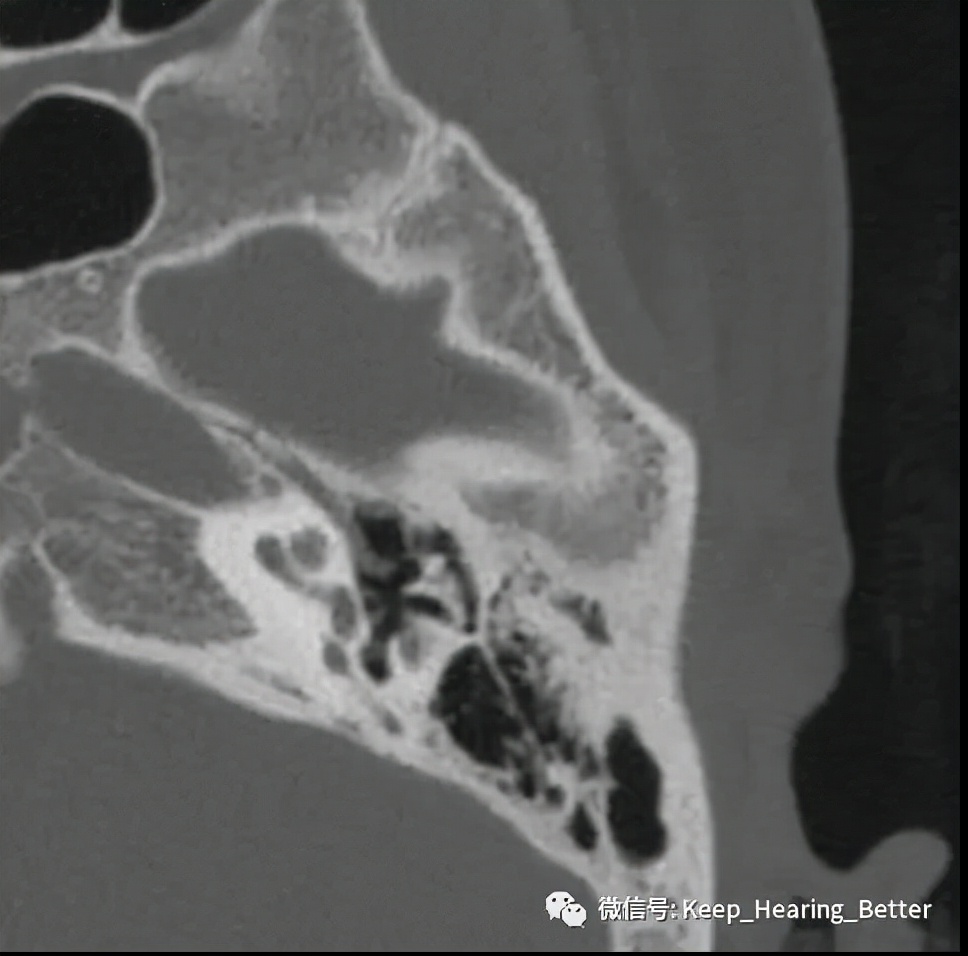

影像学检查一般选择颞骨薄层CT扫描,早期可无明显影像学阳性表现,如上图所示为此案例左耳CT影像表现。